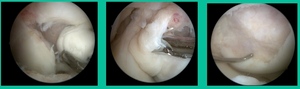

I thought I might be able to fix it. I had the conversation with the family, get in there, started taking it apart with a Vanguard elevator grasper. Behold, it’s really just cartilage fragments (Figure 2).

There’s two or three of them. We debrided it. It felt normal in six weeks, no complaints in three years. What are the results of juvenile debridement? They’re actually profoundly good. You would never expect this in the scheme of things, but the natural history of removing the piece is actually very good in the juvenile patient. However, once again, fix it if you can. Debride it, if you can’t. If they get symptoms, we restore it, and then never leave unstable fragments.